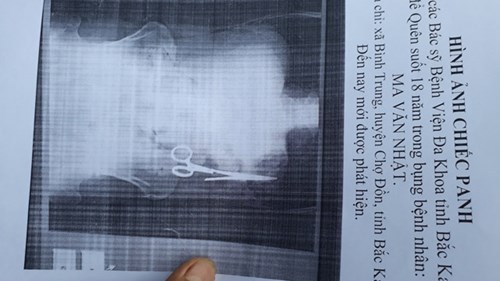

Xác minh bác sĩ quên kéo trong bụng bệnh nhân 18 năm

Bệnh viện Đa khoa tỉnh Bắc Kạn đang tiến hành xác minh việc bác sĩ phẫu thuật để quên chiếc kéo dài 15cm trong ổ bụng ông Ma Văn Nhật từ 18 năm trước.